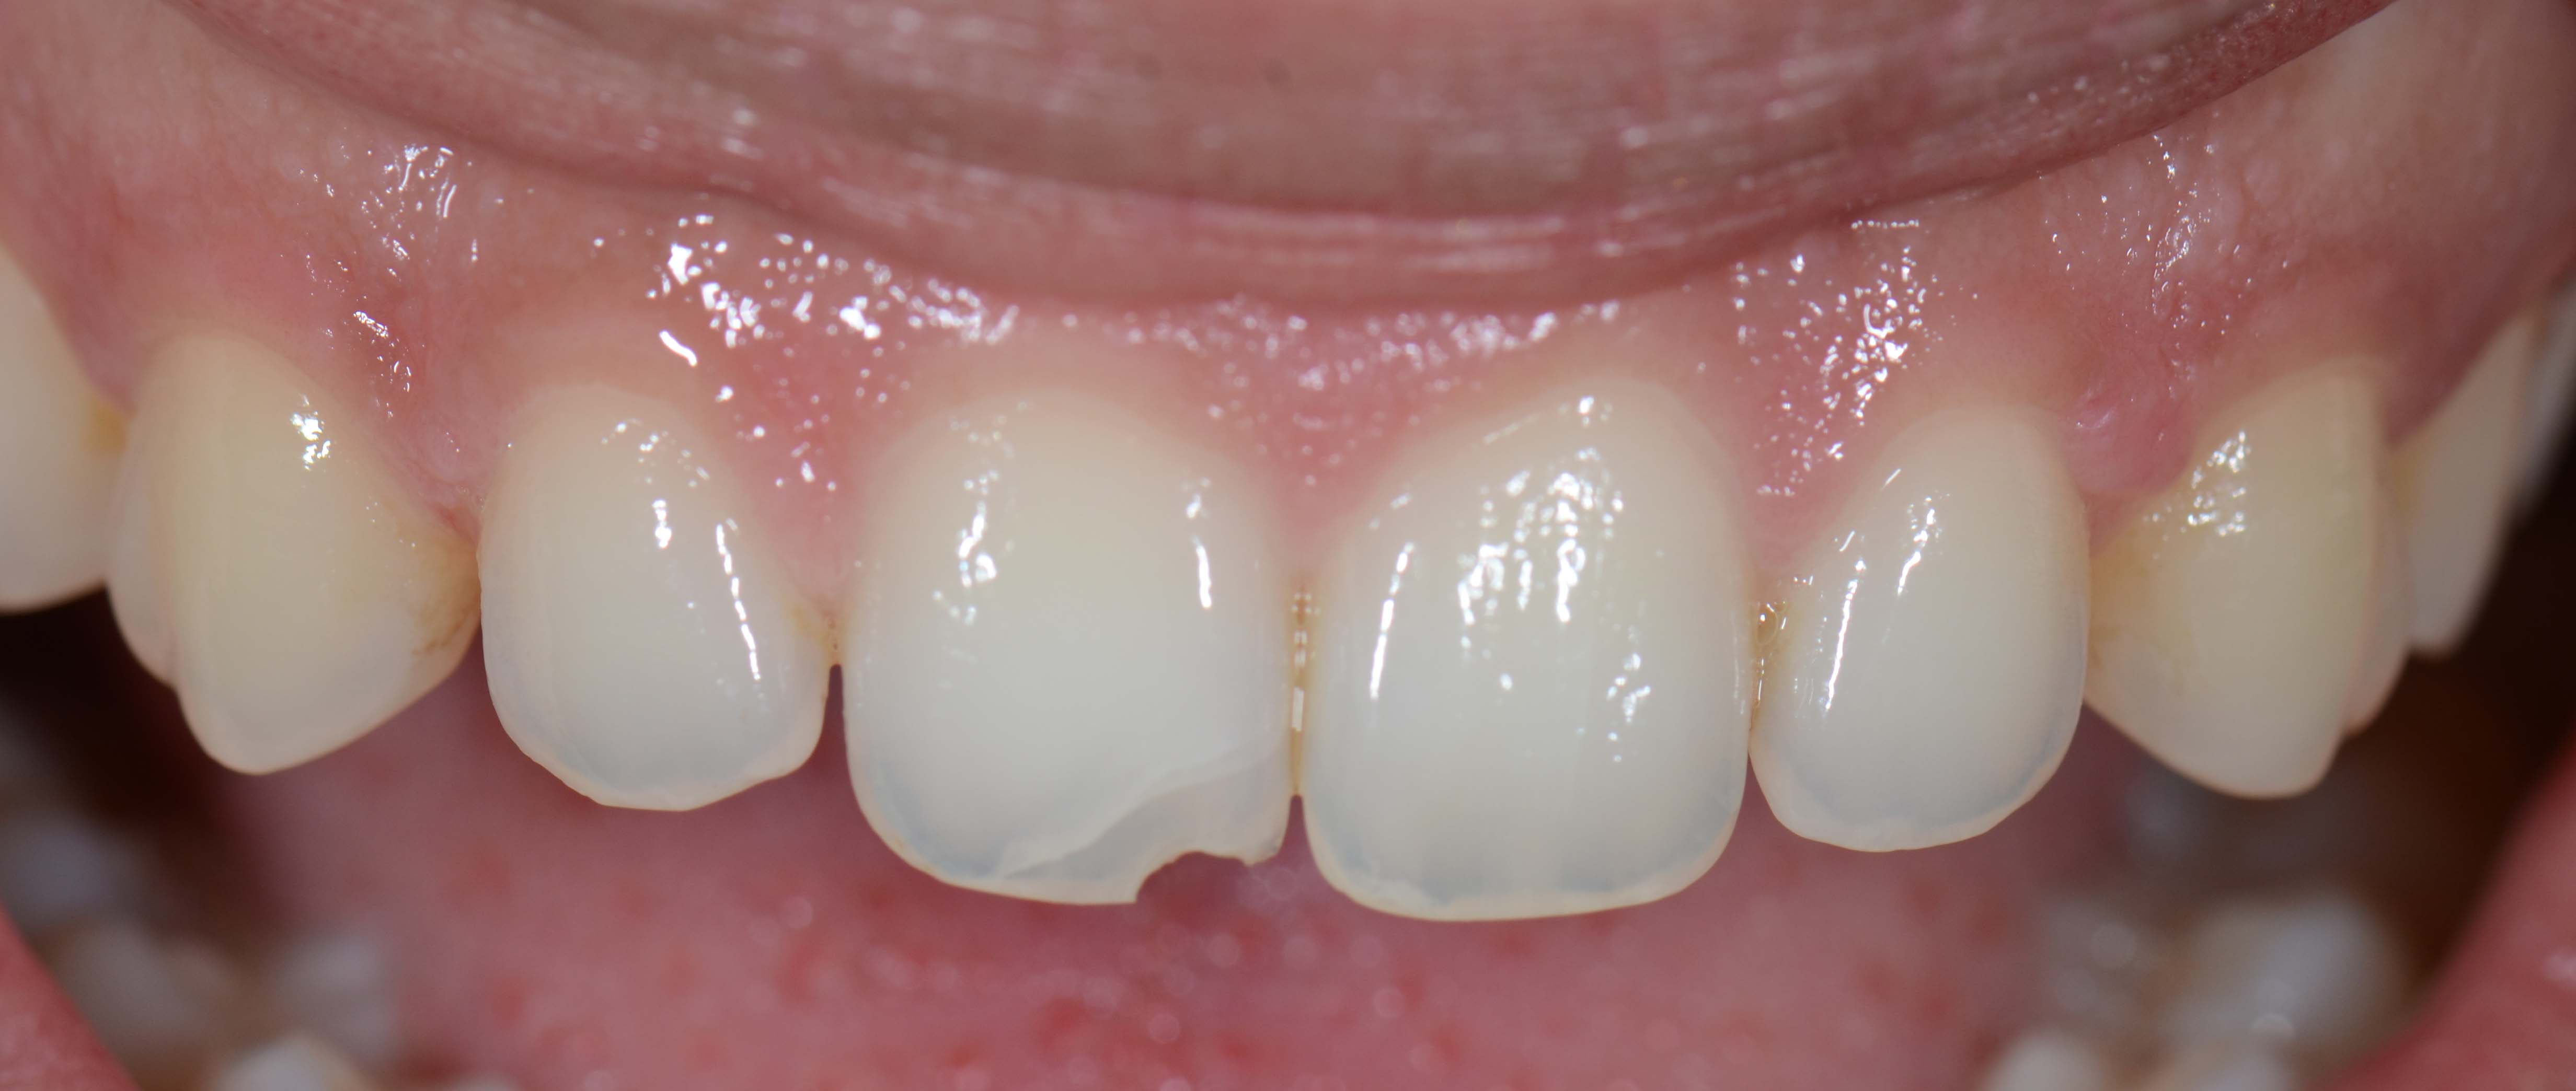

1. Exame clínico

3. Fotografias

Tratamentos urgentes serão executados se necessário, como no caso à esquerda.

SOS